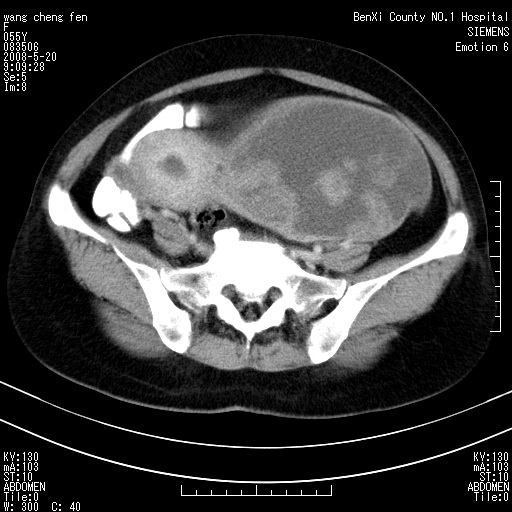

女、绝经后阴道流血3个月

左侧附件区可见一囊性占位,边缘清楚,内可见不规则形软组织影 ce:囊壁及内部可见强化 考虑 卵巢囊腺瘤

左侧附件区巨大囊实性病灶,边缘光整,病灶囊壁较厚,增强示囊壁及实性部分明显强化,强化呈度与宫体实质大致相同,宫腔积液征像,未见盆腔积液等其他异常,考虑左侧卵巢囊腺癌,不除外囊腺瘤及浆膜下肌瘤坏死

左侧附件区巨大囊实性病灶,边缘光整,病灶囊壁较厚,增强示囊壁及实性部分明显强化,强化呈度与宫体实质大致相同,宫腔积液征像,未见盆腔积液等其他异常。绝经后阴道流血3个月,结合病史左侧卵巢囊腺癌首先考虑,宫腔扩大不除外累及。期待结果。

囊实性肿块分隔厚度较大,厚薄不均,增强实性成分明显强化,有不规则阴道流血,卵巢囊腺癌可能性大。